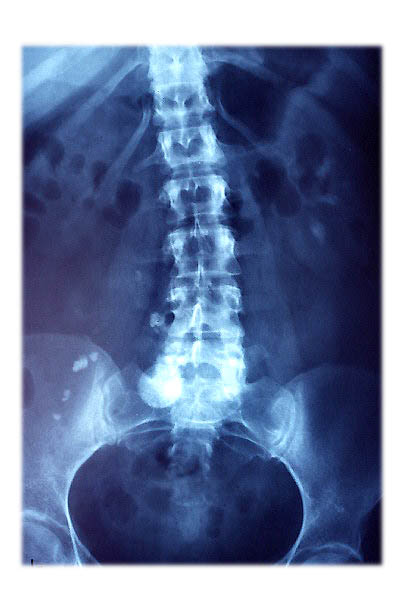

Osteoporosis. Cifosis.

Escoliosis. Espondilolistesis.

Artrosis lumbar con pinzamiento.

Artrosis lumbar

Escoliosis, artrosis, aplastamiento...